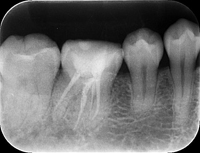

レントゲン画像

可能な限り根の細菌を減らした後、根管充填材を根に緊密に充填し、細菌が増殖し得るスペースを無くします。